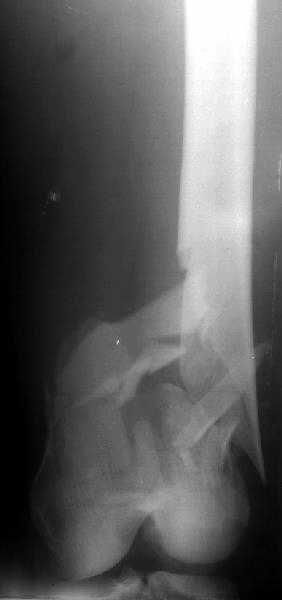

I attached an example of C2 fracture with result of the same technique in 5 months.